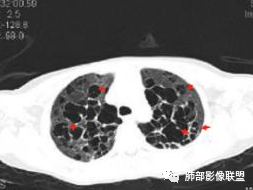

影像:双肺散在囊性病变,不规则,壁厚,部分见结节

王秀仙:

双肺多发大小不等囊腔,形态不规则,大部分囊融合,部分囊壁偏厚,部分可见磨玻璃影及多发粟粒状影,临床有交界性浆液性囊腺瘤,首先考虑囊性转移瘤,鉴别LIP,BHD。LAM,PLCH影像不符,不考虑。

晨读:女,31,间断咳嗽、咳痰9月。卵巢交界性囊腺瘤术后。胸部CT:双肺多发大小不等薄壁囊腔影,部分融合,形态不规则,个别囊壁偏厚。右肺上叶及左肺下叶纤维索条影。左下叶不规则囊腔影,壁不均匀增厚,周围不规则实性成分加GGO,放射性毛刺,胸膜牵拉。考虑:囊腔型Ca?转移?鉴别PLCH,Lam,LIp,BHD,CF,CPAM等,听大咖解析。

胸部CT:两肺多发囊腔,中上肺受累为主,囊腔形态不规则(囊有点丑),分叶状,囊壁厚薄不均,大部分囊壁薄。尚有一些结节影。